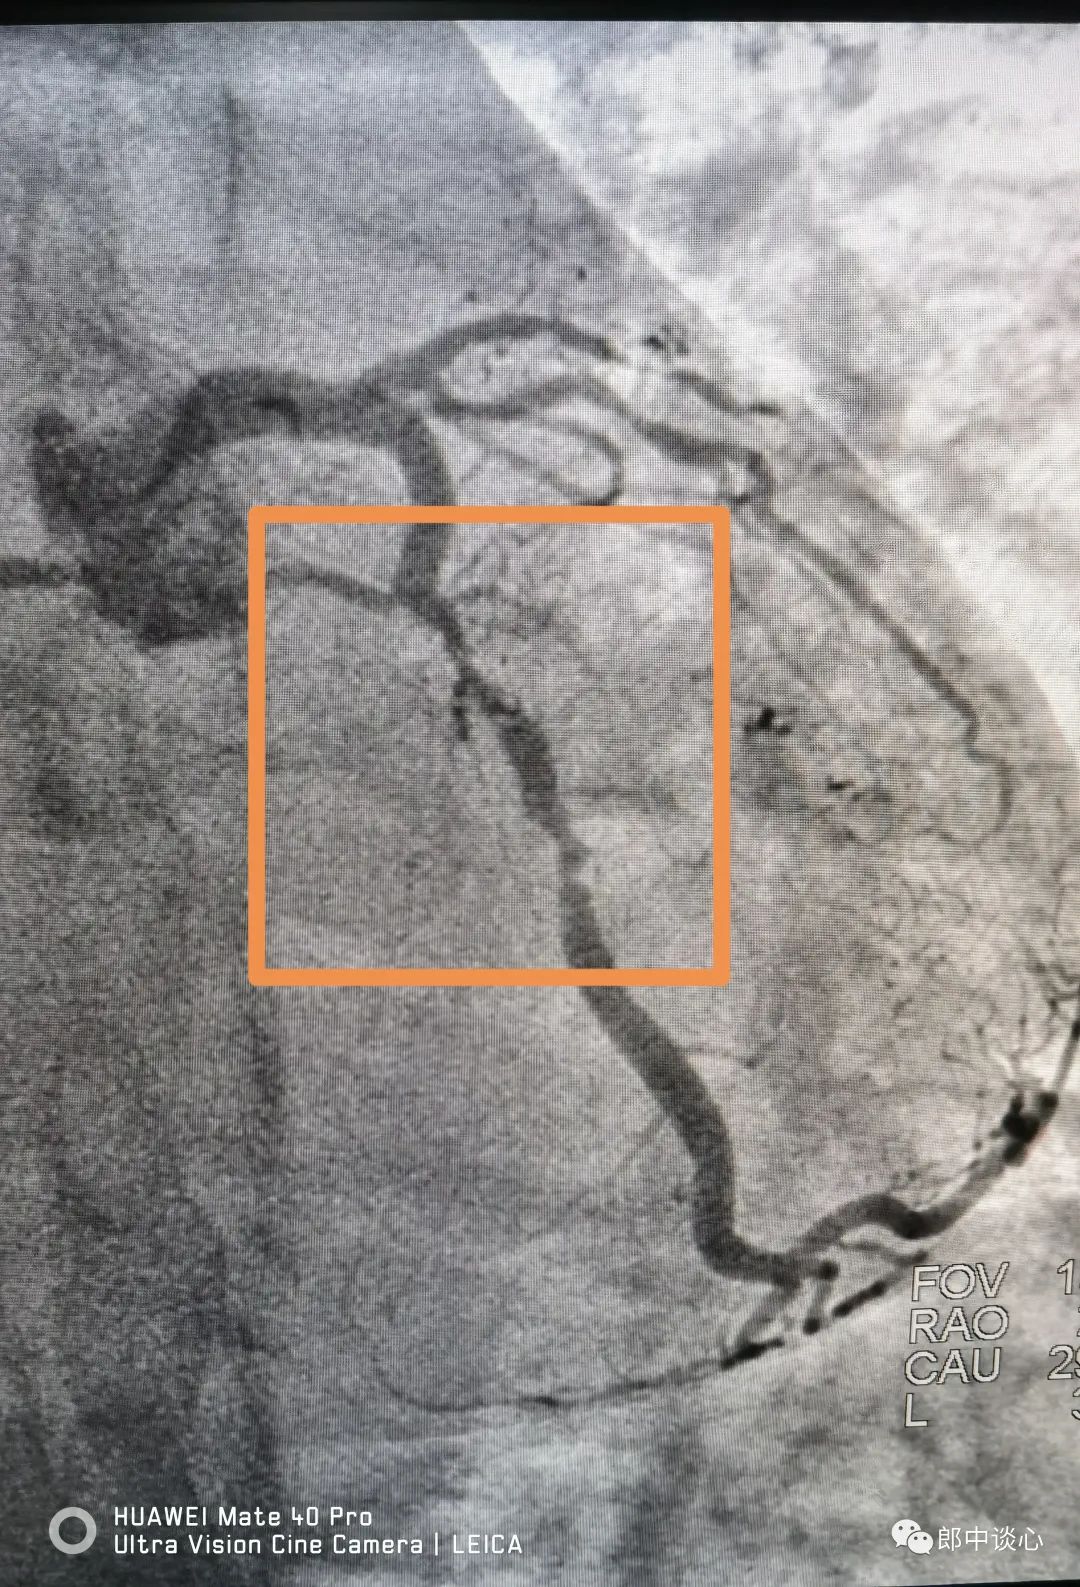

冠脉造影,果然前降支完全闭塞了!回旋支也是重度狭窄且是不稳定病变!(黄框内为病变段)